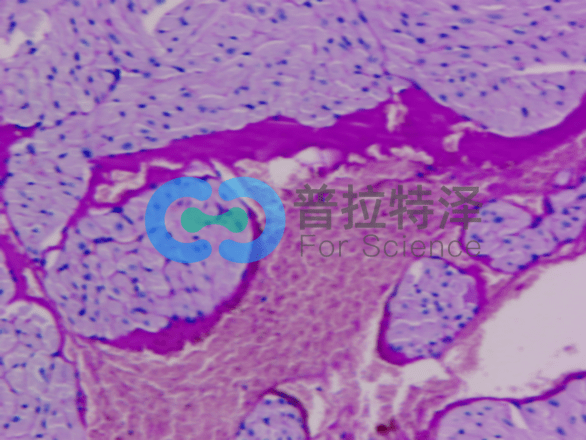

在生物學(xué)和醫(yī)學(xué)領(lǐng)域,PAS染色(Periodic Acid-Schiff Stain)是一種常用的組織染色技術(shù),用于檢測組織中的多糖類物質(zhì),如糖原和粘多糖。掌握PAS染色的正確步驟,對于科研人員和醫(yī)學(xué)工作者來說至關(guān)重要。普拉特澤生物——組織染色實驗平臺操作各類組織的染色實驗上百例,專業(yè)代做PAS染色和各種染色實驗,本文將從入門到精通,全面介紹PAS染色的步驟和注意事項。

→Schiff試劑染色:將氧化后的切片放入Schiff試劑中,醛基與Schiff試劑中的亞甲基藍發(fā)生反應(yīng),形成紫紅色產(chǎn)物。

→蘇木精復(fù)染:用蘇木精對切片進行復(fù)染,使細(xì)胞核呈現(xiàn)藍色。